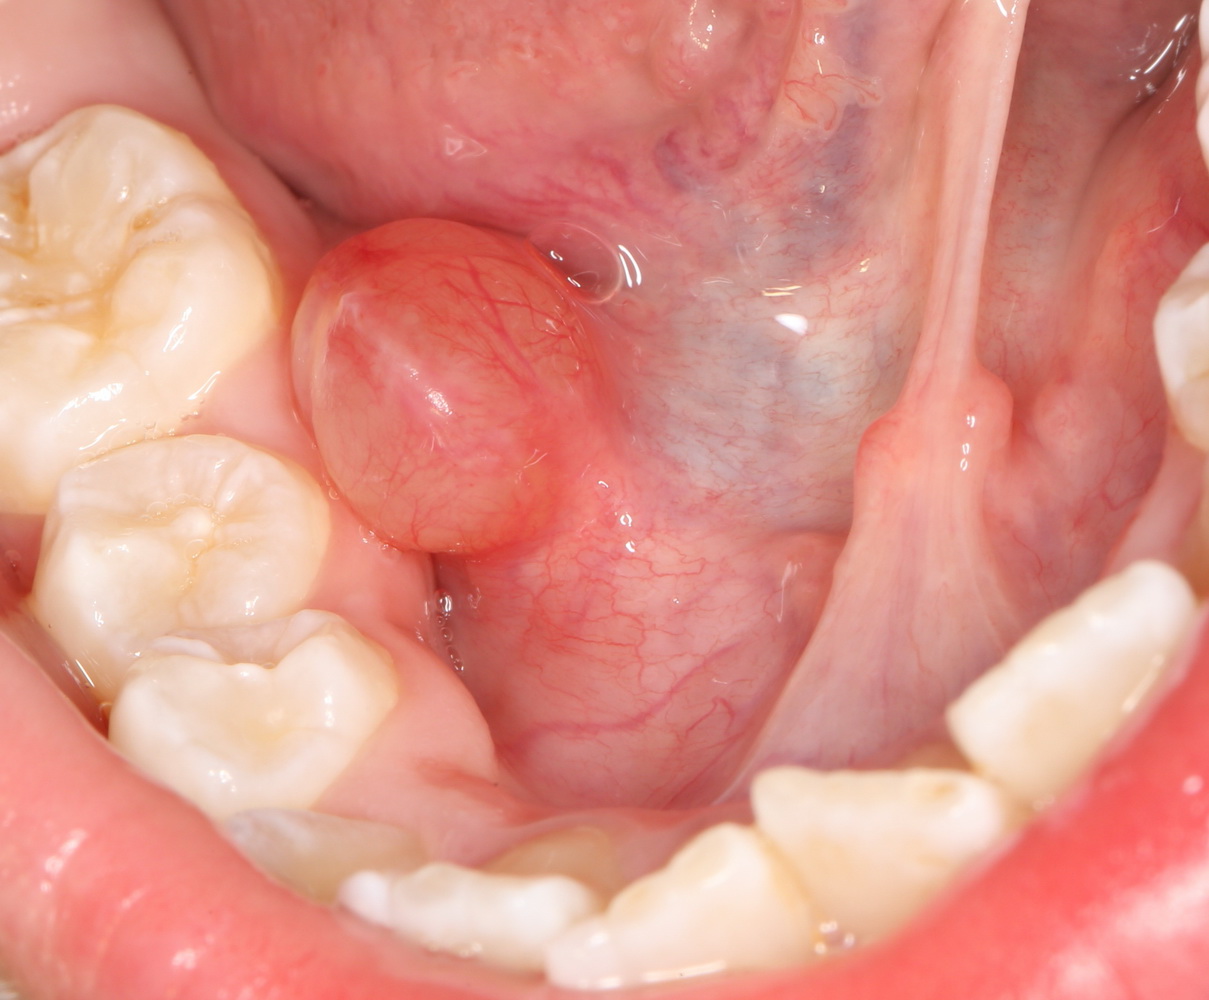

Такую работу я покажу на примере. Ко мне обратилась маленькая пациентка, девочка восьми лет с жалобами на появление новообразования под языком:

До этого они с мамой уже побывали в крупном государственном лечебном учреждении, где им поставили диагноз «ранула» и, по старой советской традиции, направили на госпитализацию и кучу анализов. Еще попутно напугали всякими страшилками, вроде того, что написал про инфекцию выше. В общем, мама девочки задумалась и обратилась ко мне.

Мы побеседовали с девочкой, она согласилась на местную анестезию. И, должен отметить, вела себя лучше некоторых взрослых.